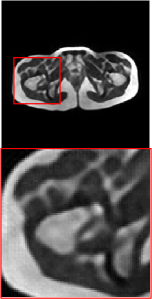

Figure 5 provides the qualitative comparison of the various methods on the four datasets at a scale of 4. The top, second, third, and bottom rows are the SR results under the FastMRI, clinical brain, clinical tumor and clinical pelvic datasets, respectively. The red boxes indicate the zoom-in region of complicated anatomical structures along with their corresponding error maps. Note that the brighter textures in the error maps, the lower the quality of the reconstructed images. As can be seen, compared to methods based on Transformers and CNNs, diffusion-based methods like DisC-Diff and DiffMSR (Ours) are capable of reconstructing high-realistic images with promising reconstruction metric scores (PSNR and SSIM). Nevertheless, while DisC-Diff can reconstruct high-precision MR images, it does not preserve the structure present in the original HR images, introducing some additional information that can affect medical diagnosis. In contrast, our method combines DM and PLWformer, which can preserve the original image’s structure while restoring high-frequency information.

In this section, we present more visual qualitative comparisons. Figures 8, 9, 10, and 11 show the reconstruction results of each method in FastMRI, clinical brain, clinical tumor, and clinical pelvic, respectively. As can be seen, although DisC-Diff can reconstruct MR images with high-frequency information, it fails to preserve the structure and content of the original Target HR image effectively, resulting in image distortion. In contrast, our proposed DiffMSR can restore high-frequency information while preserving the structure of the original HR image, indicating the effectiveness of the joint use of DM and PLWformer.